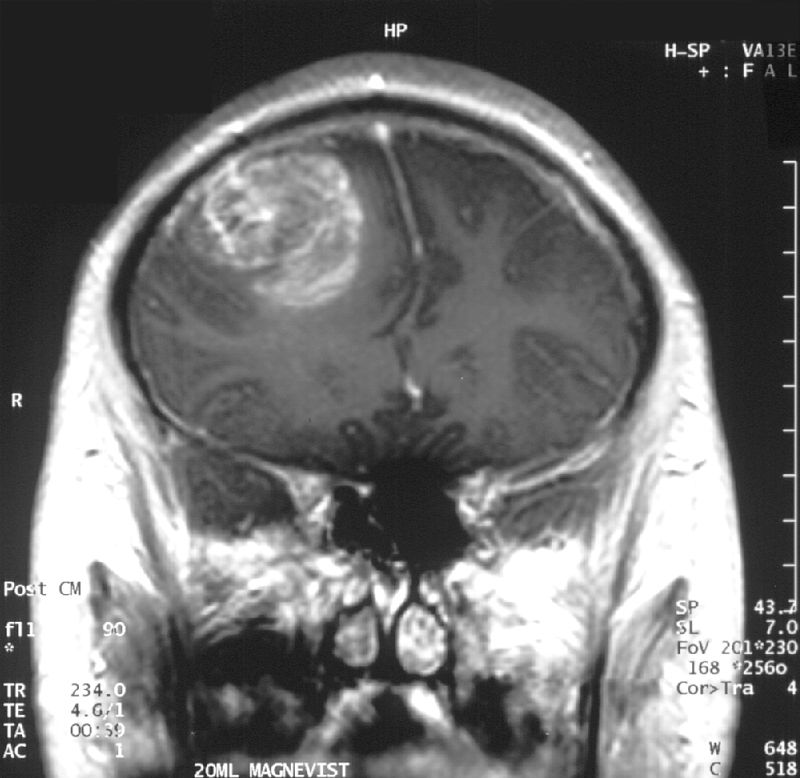

Radiology of meningiomas typically show a spherical mass linked to the dura is seen through imaging.